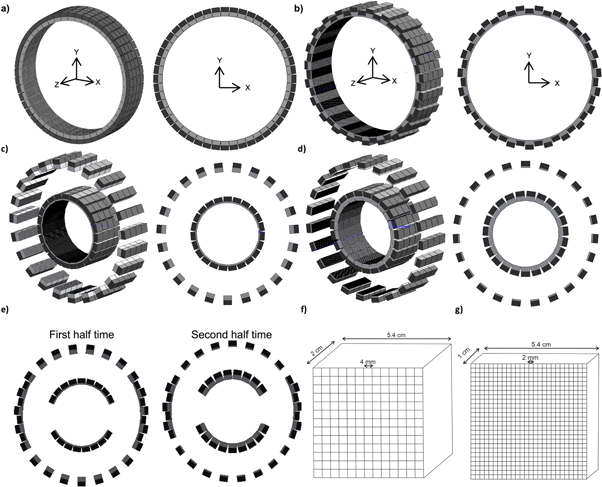

Active-PET is intended to be a switchable scanner that can be geometrically adapted to respond to users' needs and requirements (see supplemental video (available online at stacks.iop.org/PMB/67/155021/mmedia)). Active-PET has 4 rings, each including two groups of high-resolution and high-sensitivity Lutetium Oxyorthoscilicate (LSO(Ce)) pixelated detector blocks (24 for each group, overall 48 detector modules per ring), one with large pixel pitch (4 × 4 mm2) and crystal thickness (20 mm), referred to as high-sensitivity detector modules (figure 1(f)) and another one with small pixel pitch (2 × 2 mm2) and crystal thickness (10 mm), referred to as high-resolution detector modules (figure 1(g)). Furthermore, each raw of detector modules is connected to a linear motor (actuator) that can displace the detectors forward and backward in the direction of the radial axis and vary the gantry diameter to fit the object to be scanned according to the targeted application. The diameter of the gantry can change from 150 mm to 842 mm to accommodate various subjects from mice to humans. The detectors can accommodate circular, oval, and semi-planar geometries. In this work, five configurations were simulated and investigated: Large gantry with high-resolution and high-sensitivity detectors (gantry diameter = 842 mm) (figure 1(b)), small gantry with high-resolution detectors (gantry diameter = 421 mm) (figure 1(c)), small gantry with high-sensitivity detectors (gantry diameter = 421 mm) (figure 1(d)), switchable partial oval shape gantry (figure 1(e)) where the scanner shape changes during scanning by replacing high-resolution detector modules with high sensitive ones (major axes = 350 mm). To evaluate the concept of online switchable PET scanner, partial PET was defined to be switchable during scanning. This implies that during the first half of the scan, the high-resolution detectors are close to the patient whereas during the second half of the scan, the high-sensitivity detectors get close. The ROOT files of these two modes get merged and reconstructed (Brun and Rademakers 1997). The detailed specifications of each configuration along with the Biograph mCT PET scanner are summarized in table 1.

Figure 1. The 3D and 2D graphical representations of (a) the Biograph mCT and Active-PET configurations corresponding to: (b) a large gantry with high-resolution and high-sensitivity detector modules, (c) a small gantry with high-resolution detector modules, and (d) small gantry with high-sensitivity detector modules. (e) The switchable partial-ring PET scanner that can change between two different acquisition modes. (f) The high-sensitivity, and (g) high-resolution detector modules used in Active-PET. The light grey represents the crystal (with different thicknesses) while the dark grey is the photosensor (with a similar thickness).

The main idea behind the Active-PET concept lies in the use of two detector modules presenting different characteristics (high-resolution and high-sensitivity) and a dynamic gantry. In Active-PET, thick scintillator crystals with large pixel size are exploited to maintain/boost the sensitivity, whereas thin scintillator crystals with thinner and small pixel size are utilized to retain/enhance the spatial resolution. The schematics of the detectors used in these configurations are illustrated in figures 1(f) and (g).